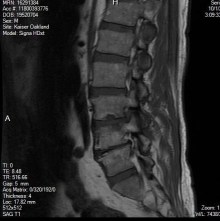

In Staley’s case, the canals between the vertebrae were narrowing, causing pressure on the spinal and nerve roots. A disc between two of the vertebrae became herniated. It bulged outward, irritating the nearby nerves. A cyst developed, further exacerbating the pain. The pain was most intense in his lower back, but it radiated outward to his hips, down his legs, all the way to his feet.

Staley and I know all this now because we read the medical report accompanying the MRI administered to Staley shortly before his surgery. But during the Year of Pain, Staley’s main awareness was that his life was changing.

Based on his X-rays and MRIs, the surgeons he consulted recommended a discectomy to remove the portion of the bulging disc, which was pressuring the nerves. They also recommended a laminotomy, to remove part of the arch of the vertebrae that had narrowed, along with the newly discovered cyst. This procedure involved using a drill and bone-biting tools to remove bone material. Staley, who fancied himself a handyman, found that part very interesting.